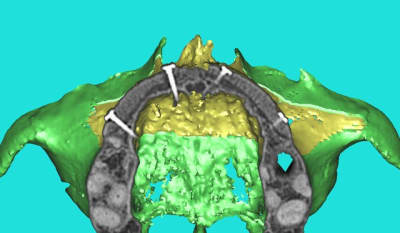

dentiste57 écrivait:

--------------------

> et là ?

> greffe selon ta méthode ?

Cross section dhvkc8 - Eugenol

3d dt3qom - Eugenol

Overview uqcp6u - Eugenol

S2y2o1v7q53ws4r5wy6ou8czrpom - Eugenol

pxav

01/05/2011 à 12h55

> dentiste57 écrivait:

> --------------------

> > et là ?

> > greffe selon ta méthode ?

expansion, c'est plus cool!